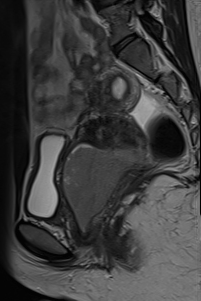

矢状位

T2

盆腔增强 MRI 检查增强了我们对 CT 扫描中发现的病变的理解。右肾发育不全,左肾肥大伴肾积水,双子宫完整,阴道隔膜,发育不全侧阴道积血。

左侧

泌尿

系统置入JJ支架,左侧输尿管下1/3扩张。

CT和MRI检查结果为Herlyn-Werner-Wunderlich综合征的典型表现,其特征为经典的三联征:III型苗勒氏管异常(完全性双子宫)、中肾管异常(肾发育不全)以及肾发育不全侧阴道积血。